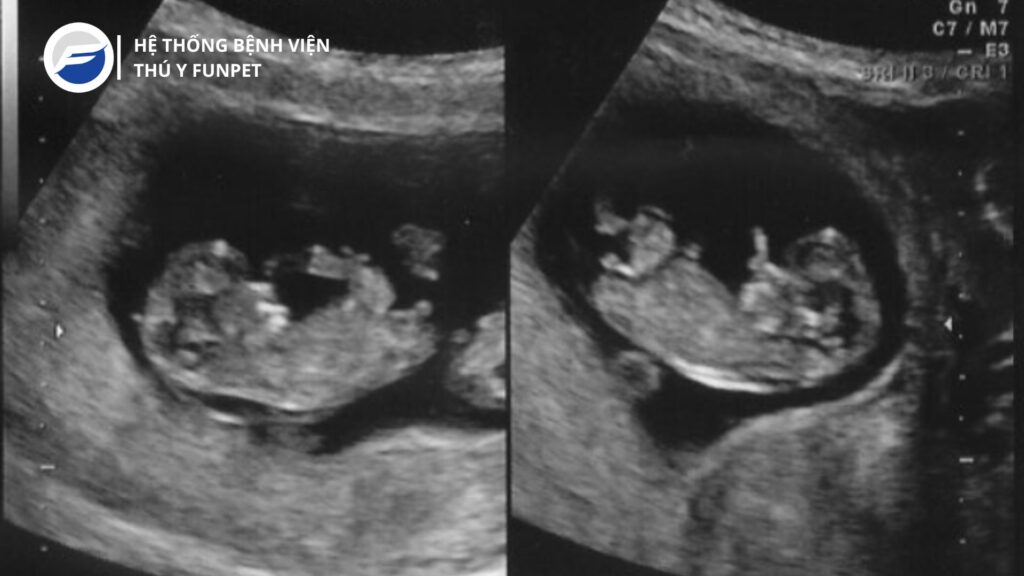

Bước 4: Phân tích kết quả Sau khi hoàn tất siêu âm, bác sĩ thú y sẽ phân tích kỹ lưỡng các hình ảnh thu được để đưa ra chẩn đoán chính xác. Siêu âm có thể phát hiện nhiều vấn đề như khối u, dị dạng, bệnh lý nội tạng, thai nhi trong trường hợp mang thai.

Khi nào nên đưa chó mèo đi siêu âm? Nên đưa chó mèo đi siêu âm trong các trường hợp sau: Nghi ngờ mang thai Theo dõi thai kỳ Có các triệu chứng bất thường như khó thở, đau bụng, tiểu tiện không bình thường Kiểm tra sức khỏe định kỳ, đặc biệt với chó mèo lớn tuổi